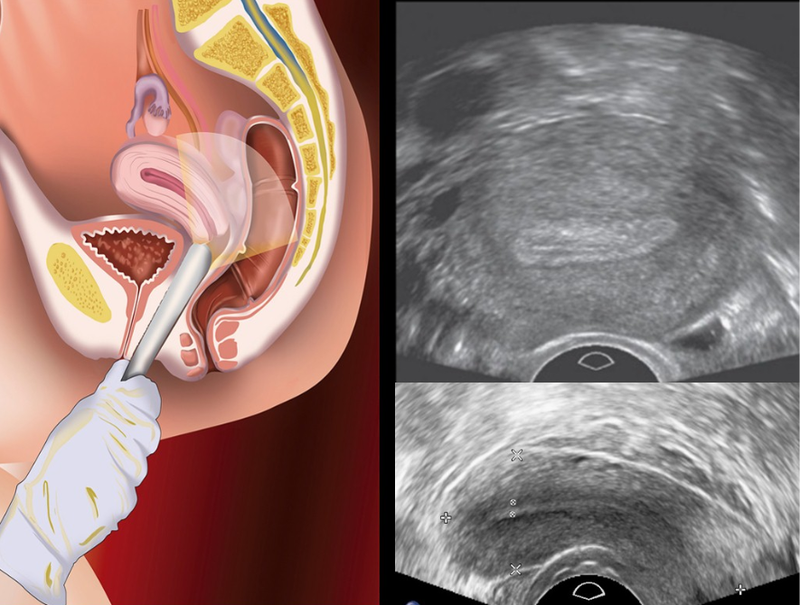

Trong phương pháp này, bác sĩ dùng một đầu dò phủ gel dẫn điện đặt trên vùng bụng bệnh nhân.

Thông qua phương pháp ngã âm đạo, một đầu dò dài, thuôn nhọn, được phủ gel dẫn điện và được bảo vệ bằng vỏ bọc (bao cao su) sẽ được đưa vào âm đạo.

Tùy vào lý do siêu âm mà bác sĩ sẽ chọn lựa giữa phương pháp siêu âm vùng bụng hay ngã âm đạo. Một số trường hợp cần tiến hành cả hai phương pháp để giúp việc chẩn đoán hoặc điều trị được tối ưu nhất.

Hiện nay, siêu âm vùng chậu có thể được thực hiện theo ba hình thức sau đây:

Bác sĩ dùng đầu dò được di chuyển trên vùng bụng dưới của bệnh nhân để tìm u xơ tử cung lớn hoặc một số vấn đề khác trong khung chậu của cả nam và nữ.

Đây là kỹ thuật đầu dò được áp dụng để kiểm tra các vấn đề ở nam giới hoặc nữ giới. Thông thường, phương thức siêu âm này được thực hiện phổ biến nhất ở nam giới khi cần đánh giá vùng chậu, chủ yếu là tuyến tiền liệt và túi tinh.

Đầu dò của máy siêu âm được đưa vào âm đạo của nữ giới để đánh giá khả năng sinh sản hoặc mang thai. Bên cạnh đó, siêu âm vùng chậu cũng được bác sĩ chỉ định trong các trường hợp khác như: Tìm dụng cụ tử cung, đánh giá sự tăng trưởng của khối u, theo dõi sự tăng trưởng của thai nhi ở phụ nữ mang thai, xác nhận thai có nằm trong tử cung hay không,... Trong một số trường hợp cần lấy mẫu sinh thiết, bác sĩ cũng có thể sử dụng phương pháp siêu âm.